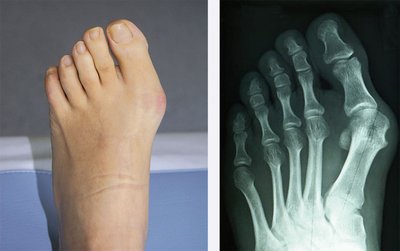

Unter den erworbenen Erkrankungen zählt der Spreizfuß in den Industrieländern zur häufigsten Fußdeformität. Er tritt bei Frauen deutlich häufiger auf als bei Männern. Auch hier spielt das Schuhwerk eine große Rolle – je höher der Absatz, desto wahrscheinlicher wird ein Spreizfuß. Die Therapie der Wahl ist zunächst das konservative Vorgehen. Es sollte weiches, niedriges Schuhwerk getragen werden, gegebenenfalls benötigt der Patient Einlagen oder sogar orthopädisches Schuhwerk. In Verbindung mit dem Spreizfuß findet man sehr häufig den Hallux valgus, umgangssprachlich auch Ballenfuß genannt oder Hammer- und Krallenzehen. In frühen Formen stehen auch hier konservative Maßnahmen im Vordergrund. Treten erhebliche Schmerzen, insbesondere Belastungsschmerzen, hinzu, lässt sich eine korrigierende Operation meist nicht vermeiden. In der Klinik für Orthopädie und Unfallchirurgie des Mediclin Krankenhauses am Crivitzer See werden diese Eingriffe häufig durchgeführt. Im Anschluss an die unmittelbare Nachbehandlung kann zügig konfektionier-

tes Schuhwerk problemlos getragen werden.